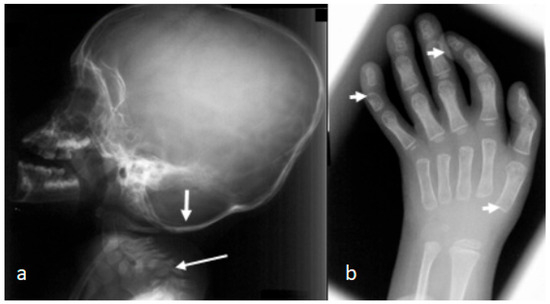

In these children, dysmorphic facial features were evident, which encompassed distinctive facial features, frontal bossing, and a flattened nasal bridge giving the facial phenotype of a dish-like facies. Our orthopedic strategy is based upon detailed clinical and radiological phenotypic characterization. Radiological phenotypic interpretations have been organized for all children by referring to 3D CT scan. In a lateral skull radiograph of a 7-month-old boy with Larsen syndrome, one can note brachycephaly, frontal bossing, and marked disproportionate small facial bones in comparison with a large cranium and dysplastic cervical spine, osteopenia of the lambdoid bones causing downward bulging, and prominence of the occipital bone associated with progressive thinning of the squamous part of the occipital bone (arrow). One can also note the cervical kyphosis (arrow) AP hand radiograph of a 3-year-old boy with Larsen syndrome showing retarded bone age, expansion of the distal ends of the shortened metacarpals, a thumb proximally placed, and the presence of accessory bone adjacent to the distal third metacarpal-phalangeal bone (arrow). One can also see the delta phalanx of the middle metacarpophalangeal bone of the fifth finger (arrow) (b) (Figure 1a,b). The AP pelvis radiograph of a 7-month-old girl with Larsen syndrome showed bilateral hip dislocation associated with maldevelopment of a severely dysplastic acetabulum and dysplastic capital femoral epiphysis (a). The AP pelvis radiograph of a 3-year-old boy with Larsen syndrome showed bilateral hip dislocations (severe acetabulo-femoral dysplasia) (Figure 2a). The AP pelvis radiograph of a 7-month-old girl with Larsen syndrome showed bilateral hip dislocation associated with maldevelopment of a severely dysplastic acetabulum and dysplastic capital femoral epiphysis (a). The AP pelvis radiograph of a 3-year-old boy with Larsen syndrome showed bilateral hip dislocations (severe acetabulo-femoral dysplasia) (Figure 2b). AP knees radiograph of a 5-month-old boy with Larsen syndrome showing bilateral knee dislocations (arrows) associated with under tubulation of the tibae and fibulae. Note the fragmented/deformed epiphyses and that the right tibia is medially subluxated. Note bilateral talipes equinivarus associated with double ossifications of the calcaneus (arrows) (Figure 3).

Figure 1.

(a,b): Lateral skull radiograph of a 7-month-old boy with Larsen syndrome. Note brachycephaly, frontal bossing, and marked disproportionate small facial bones in comparison with a large cranium and dysplastic cervical spine, osteopenia of the lambdoid bones causing downward bulging, and prominence of the occipital bone associated with progressive thinning of the squamous part of the occipital bone (arrow). Note the cervical kyphosis (arrow) AP hand radiograph of a 3-year-old boy with Larsen syndrome showing retarded bone age, expansion of the distal ends of the shortened metacarpals, a thumb proximally placed, and the presence of accessory bone adjacent to the distal third metacarpal-phalangeal bone (arrow). Delta phalanx of the middle metacarpophalangeal bone of the fifth finger (arrow) (b).